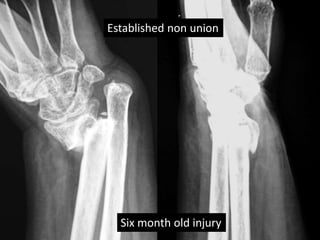

Case two

• 50 years old female

• Low energy injury

• Sustained fracture lower end radius

• Pop cast for six weeks

• Progressively increasing deformity following

removal of plaster.

• X- rays after six months following fracture

showing non-union.

Established non union

Six month old injury